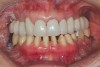

Figure 30  Final restorations.

Figure 30

Figure 31  Technical precision and artistic skill blend into a pleasing smile and a happy patient.

Figure 31